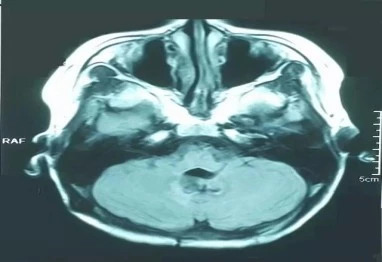

淄博万杰质子中心-典型质子治疗案例——儿童髓母细胞瘤时间:2024-08-24 淄博万杰质子中心-典型质子治疗案例——儿童髓母细胞瘤 髓母细胞瘤质子治疗病例:患者 男 10岁2005年1月因“间断头疼呕吐1月”入住某儿童医院,MRI检查示:第四脑室占位并脑积水,2005年2月在该院全麻下行“第四脑室肿瘤切除术”,术中见:肿瘤于脑干、小脑粘连,并把四脑室侧孔及导水管浸润填塞。肿瘤灰红色,无包膜,术后病检示:大细胞髓母细胞瘤。2005年3月行术后全中枢调强放疗DT36GY/18F,并给予小脑局部推量DT16GY/8F,过程顺利。2005年5月行MRI示:第四脑室占位,符合髓母细胞瘤表现,全脊髓未见确切异常。 2006年2月行MR提示复发,为进一步诊治来博拉格质子治疗中心就诊,经博拉格质子中心专家会诊,质子治疗与普通放疗相比较,优势明显,建议行局部质子治疗,可保护脑干、小脑等正常组织,特别是对于儿童肿瘤、放疗后复发肿瘤优势明显; 质子治疗前MRI检查图像:可见第四脑室明显占位